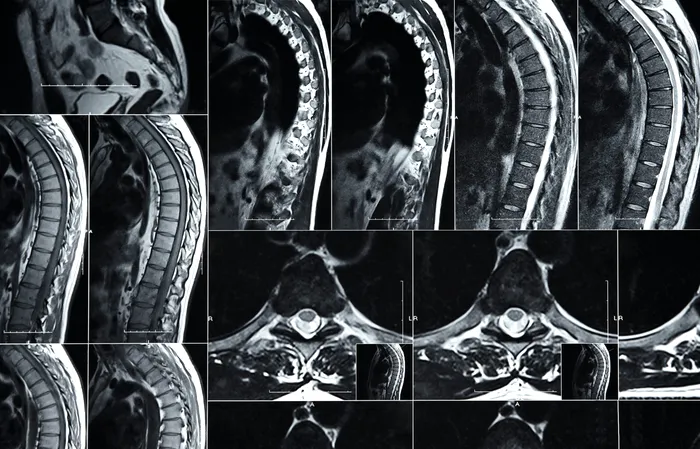

Sursa foto: Envato